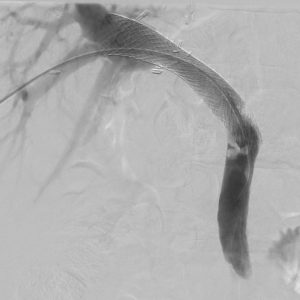

2. BRTO / PARTO Procedure

The Problem: Gastric varices (dilated veins in the stomach wall) have a high risk of severe, often fatal, bleeding and are difficult to treat with standard methods.

Our Solution: BRTO (Balloon-occluded Retrograde Transvenous Obliteration) and its modern variant PARTO (which uses a plug instead of a balloon) are techniques to block and fill these fragile veins with sclerosing agent, causing them to clot and shrink.

Patient Benefit: A targeted, minimally invasive solution to prevent and treat life-threatening bleeding from gastric varices.